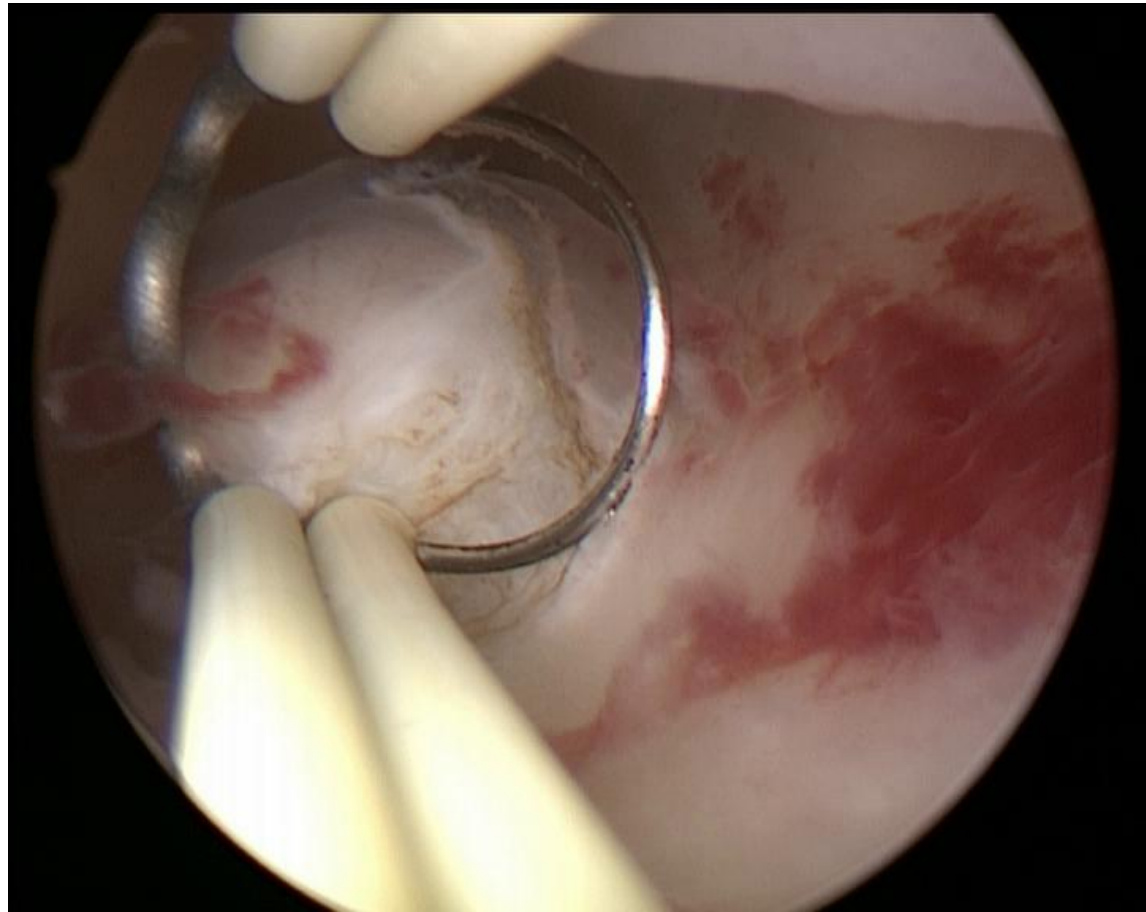

CASE 1 Control group

案例1 对照组

Prompt: Please tell me what the silver surgical instrument in the picture is and its purpose.

提示:请告诉我图片中的银色手术器械是什么及其用途。

GPT-4V Response:

GPT-4V 响应:

• response 1: The image shows a certain surgery being performed under arth ros copy. From the image, surgical instruments can be seen, one of which looks like a clamp or manipulator. Regarding the specific type of surgical instrument, I cannot be completely sure, as this depends on the specific purpose and context of the surgery. Art hr osco pic surgeries are generally used for diagnosing and treating joint problems, especially in the knee, shoulder, and other major joints. The purpose of this instrument may include manipulating tissues, excising damaged tissues, clamping certain objects, etc., depending on the purpose of the surgery.

• 回应1: 图像显示在关节镜 (arthroscopy) 下进行的某种手术。从图像中可以看到手术器械,其中一件看起来像钳子或操作器。关于具体的手术器械类型,我无法完全确定,因为这取决于手术的具体目的和背景。关节镜手术通常用于诊断和治疗关节问题,尤其是膝关节、肩关节等主要关节。该器械的用途可能包括操作组织、切除受损组织、夹持特定物体等,具体取决于手术目的。

response 2: The image shows a scene from an endoscopic surgery. The surgical instrument looks like a ring-shaped grasper or clamp. This type of instrument is typically used to grasp, excise, or manipulate tissue in art hr osco pic or other endoscopic surgeries. The red area in the picture might be tissue inside the joint cavity, and the white structures might be bone or cartilage, but this requires more detailed background information to determine. The specific purpose of this instrument depends on the type and purpose of the surgery, such as in knee arth ros copy, it might be used to excise damaged cartilage or repair injured ligaments.

回复2:图像显示的是内窥镜手术场景。手术器械呈环形抓钳或夹钳状,这类器械通常用于关节镜(arthroscopic)或其他内窥镜手术中抓取、切除或操作组织。图中红色区域可能是关节腔内组织,白色结构可能是骨骼或软骨,但需更详细的背景信息才能确认。该器械的具体用途取决于手术类型和目的,例如在膝关节镜手术中,可能用于切除损伤软骨或修复受损韧带。

response 3: The image shows an instrument used in an art hr osco pic surgery. Art hr osco pic surgery is a method that enters the joint cavity through small incisions and uses an art hro scope for diagnosis and treatment. The instrument in the picture might be used to clamp, cut, or refine tissues inside the joint. Specifically, the middle ring-shaped structure might be a protective sleeve, used to protect the soft tissues inside the joint from damage. The clamping instruments on both sides might be used to manipulate tissues inside the joint or perform surgical operations.

回复3:图中展示的是用于关节镜手术的一种器械。关节镜手术是通过小切口进入关节腔,利用关节镜进行诊断和治疗的方法。图中的器械可能用于钳夹、切割或修整关节内部组织。具体而言,中间的环形结构可能是保护套,用于保护关节内部软组织免受损伤。两侧的钳夹器械可能用于操作关节内部组织或进行手术操作。

CASE 1

案例 1

Providing the tasks

提供任务

Prompt: This image is from a hy ster osco pic myomectomy surgery. Please tell me what the silver surgical instrument in the picture is and its purpose.

提示:这张图片来自宫腔镜子宫肌瘤切除术。请告诉我图中银色手术器械的名称及其用途。

response 1: The image appears to be from a hy ster osco pic procedure, specifically a hy ster osco pic myomectomy, as you mentioned. The ring-shaped surgical instrument visible in the image is known as a "loop electrode" or "re sec to scope loop." The purpose of this loop electrode in a hy ster osco pic myomectomy is to resect or cut away fibroids (myomas) from the inner lining of the uterus. The loop electrode is electrified, and when it comes in contact with the fibroid tissue, it can cut and coagulate (stop bleeding) simultaneously. This allows the surgeon to carefully and selectively remove the fibroid tissue without damaging the surrounding healthy tissue of the uterus. response 2: The image appears to be from a hy ster osco pic procedure, specifically a myomectomy, which involves the removal of fibroids from the uterus. The ring-shaped surgical instrument you’re referring to is likely a "loop electrode" or "re sec to scope loop". This instrument is used in hy ster osco pic surgeries to cut tissue and/or coagulate bleeding vessels. When electrical current is passed through the loop, it can effectively cut tissue or coagulate blood vessels to control bleeding. In the context of a hy ster osco pic myomectomy, the loop electrode is used to shave off or resect pieces of the fibroid until it has been completely removed or reduced in size. response 3: The image appears to show a surgical procedure inside a uterus using hysteroscopy. The ring-shaped instrument you’re referring to is likely a myoma loop or a re sec to scope loop. Its primary purpose is to resect (or cut away) tissue, such as fibroids (myomas) from the inner wall of the uterus. During a hy ster osco pic myomectomy, the surgeon uses this loop to shave off the fibroid tissue in small portions until the fibroid is entirely removed. The loop typically carries electrical current, which helps in cutting and coagulating the tissue, minimizing bleeding during the procedure.